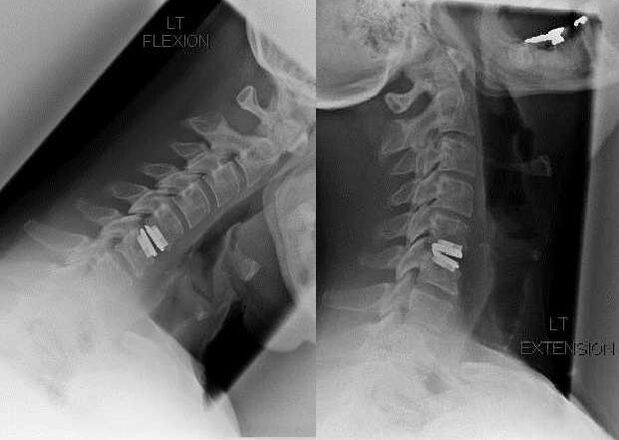

Surgery

Indications for surgery include ineffectiveness of conservative treatment, as well as complications of cervical osteochondrosis, for example, disc myelopathy, vertebral artery syndrome and radicular syndrome.To decompress the spinal cord, blood vessels and spinal roots, the following operations are performed:

During surgery, bone fragments and ligaments may be removed, and the intervertebral discs may be completely or partially removed.For small herniated protrusions, laser ablation of the disc core is often performed.

After resection of the vertebral structures, stabilization of the motion segments of the spine with spinal fusion or installation of bone and skin autografts is often required.